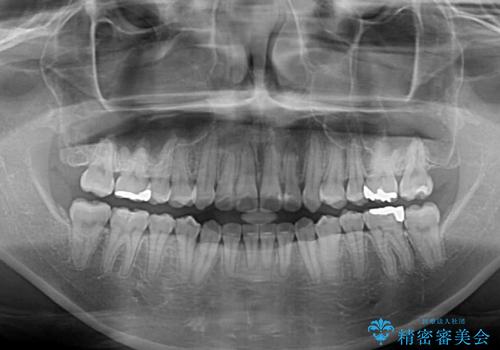

- 前歯のデコボコを気にして来院された患者様です。

前歯のデコボコはもちろん気になるところですが、舌の突出癖により上下前歯が非接触となっている状態でした。

上下前歯が非接触である開咬は、インビザラインによる治療がお勧めではありますが、しっかりと使う自信がないとのことで、ワイヤー装置にて治療を行うこととしました。

デコボコはあっという間に改善されましたが、開咬の改善に時間がかかりました。

舌の突出癖改善のトレーニングをしっかりと行っていただき、上下前歯が接触する咬み合わせを達成することができました。